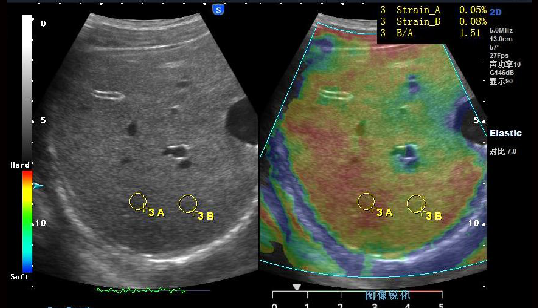

Elasticity imaging: 弹性成像

Freehand elasticity imaging: 徒手弹性成像(FEI)

基于应力的弹性应变成像,提供组织软、硬病变的诊断信息

• 徒手弹性成像是通过移动探头对检测部位进行挤压使组织产生运动,并利用回 波信号进行运动检测得到表征组织弹性的应变图像

• 业界最高帧率 50fps vs 20fps

• 业界最大检测区域—全器官检测